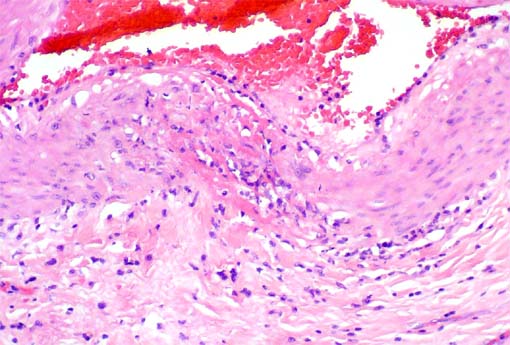

Figura 4.

H&·, X200.